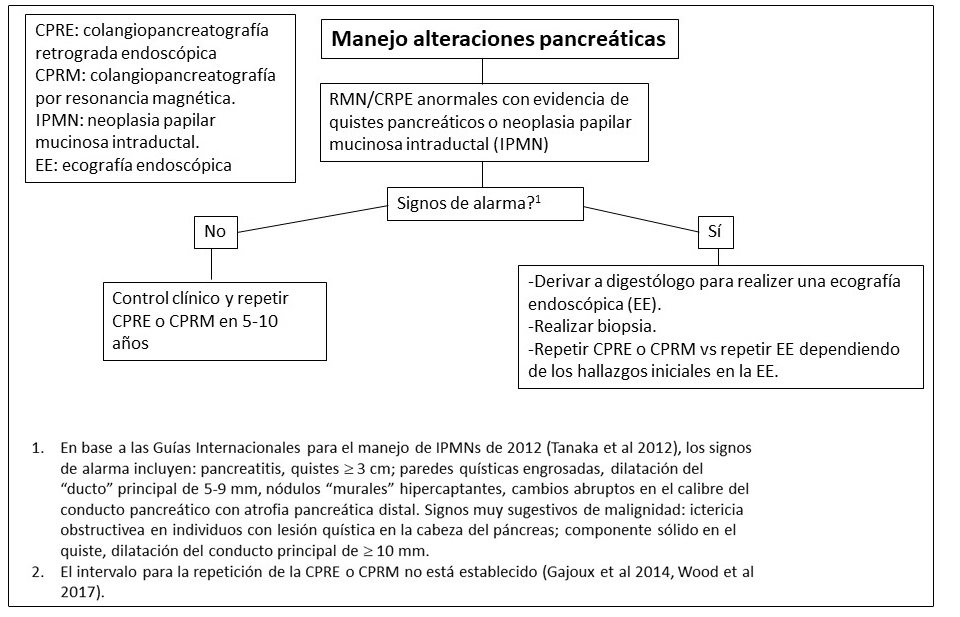

Afectación pancreática.

Aproximadamente un 15% de los individuos con DF/MAS presentan alteraciones pancreáticas incluyendo:

- Pancreatitis

- Neoplasias mucinosas papilares intraductales (IPMN), las cuales pueden presentar diversos grados de displasia (Gaujoux et al 2014, Wood et al 2017).

- Se ha reportado un caso de un paciente con un carcinoma pancreático derivado de un subtipo de IPMN intestinal (Parvanescu et al 2014).

- Tanaka et al 2012.

Figura 17. Recomendaciones para el manejo de alteraciones pancreáticas en pacientes con Displasia Fibrosa/Síndrome de McCune-Albright